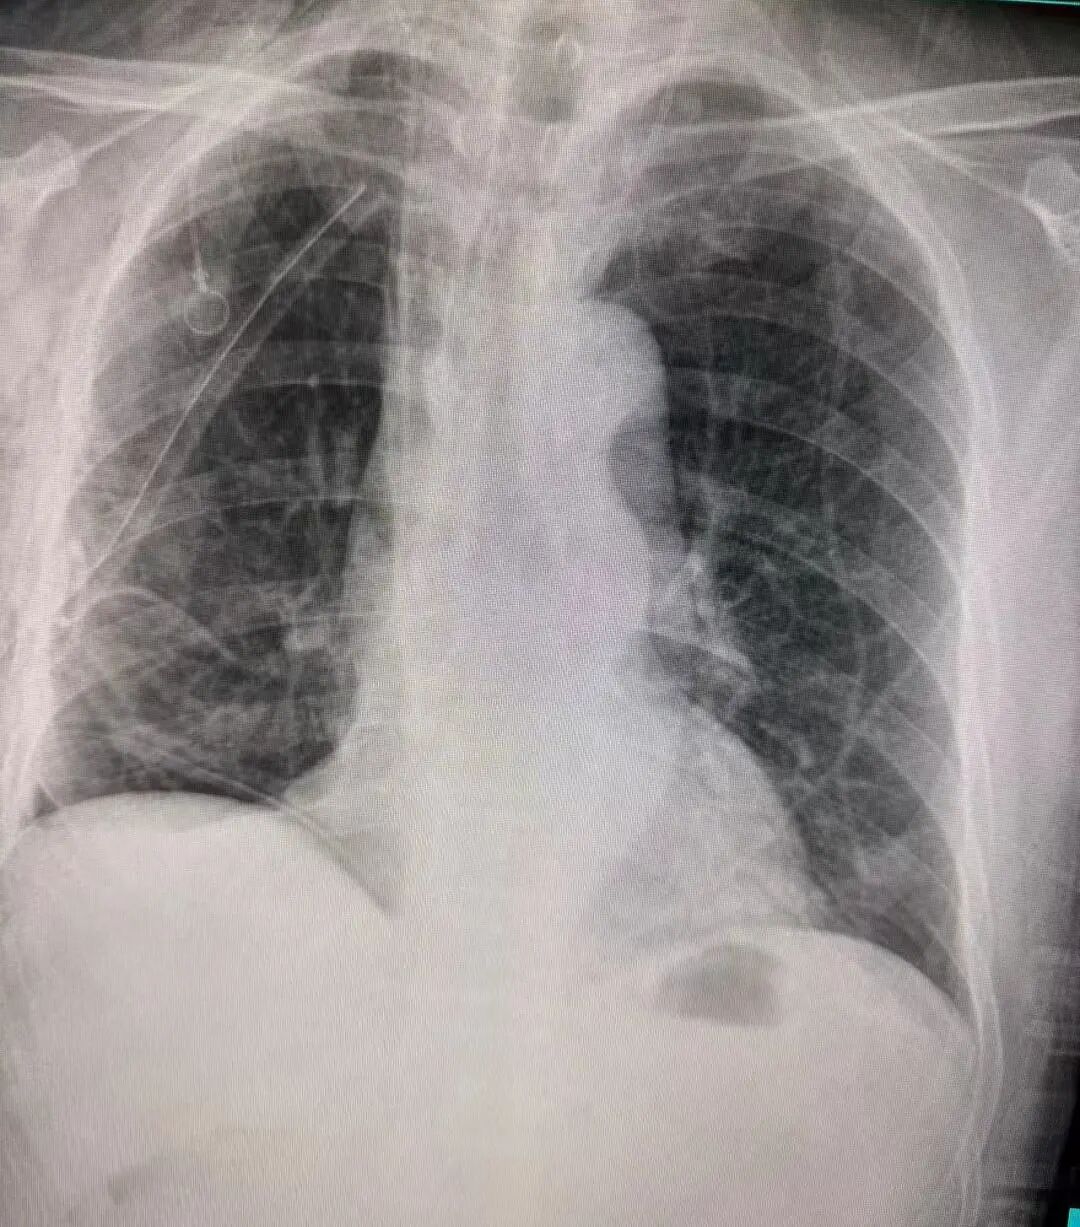

术后胸片显示右中下肺叶已切除,胸腔形态规整

引流管位置良好,肺部复张情况理想